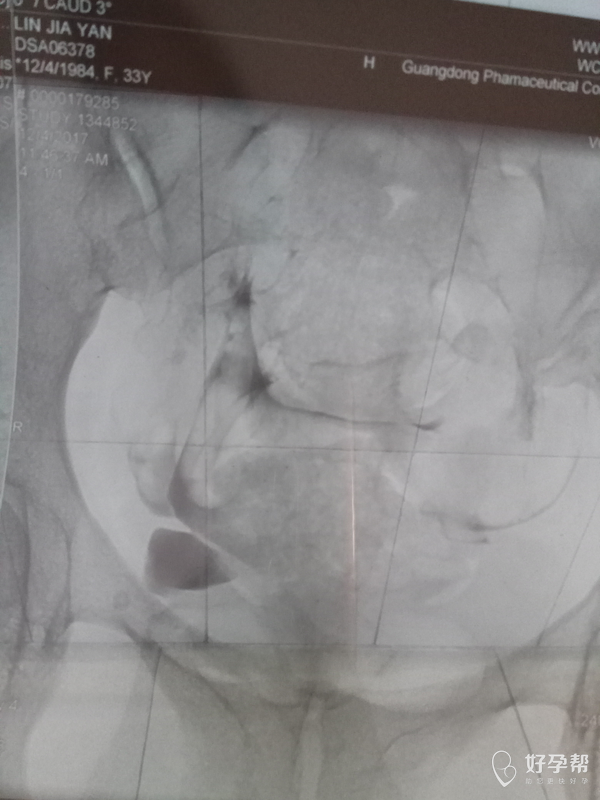

医生帮我看看造影照片,

这是碘油造影吧,双侧输卵管都是通畅的,建议积极试孕,祝好孕